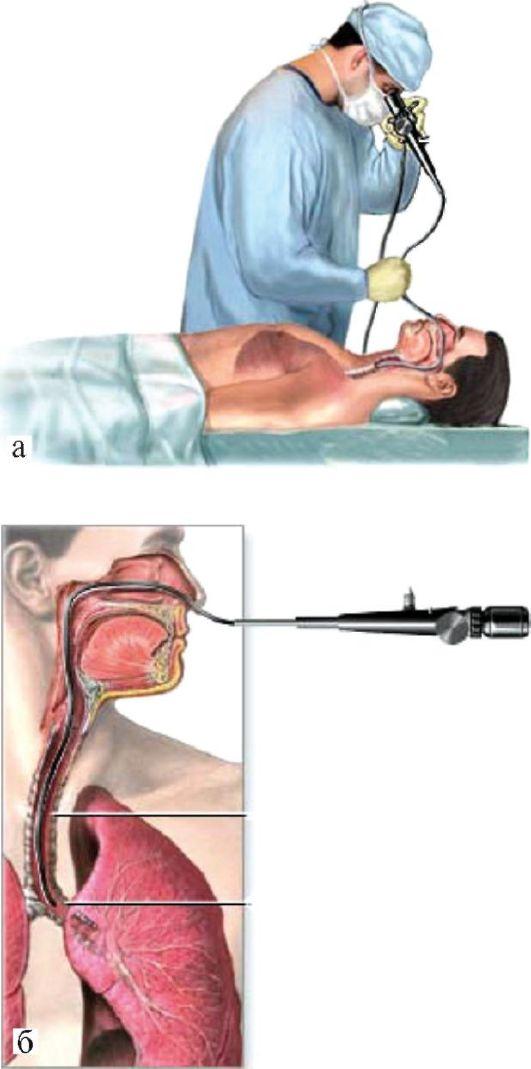

Фотографии и информация о бронхоскопии при туберкулезе